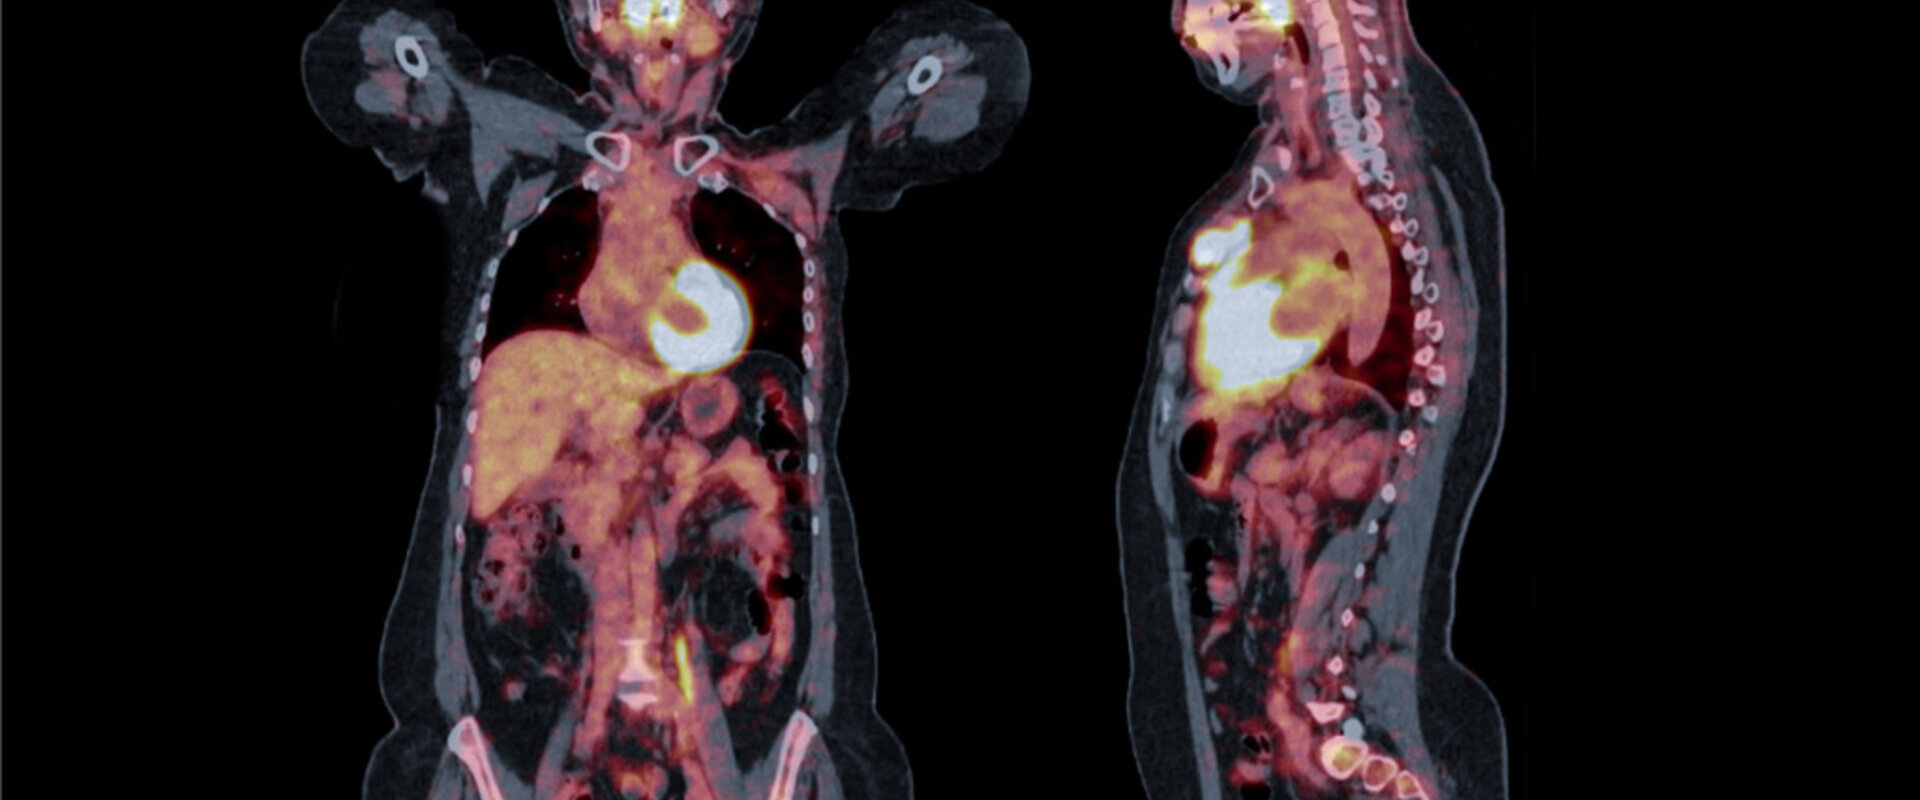

Over a third of all deaths in the EU are caused by disorders of the heart or blood vessels collectively described as cardiovascular disease (CVD), making it the leading cause of mortality. As well as the significant social toll, CVD is also estimated to cost the EU economy around €210 billion a year. The current ‘gold standard’ method to diagnose CVD, and hence direct appropriate treatment, is through measuring the blood flow or ‘perfusion’ in affected organs and tissue using Positron Emission Tomography (PET). In this technique a radionuclide is injected into a patient and the perfusion monitored using a PET scanner. From this scan, an image or cardiac perfusion map is derived which is used to make clinical decisions. The assessment of PET perfusion is usually performed quantitatively using specific cut-off thresholds by visual inspection or by describing the image intensity, however the measurement uncertainties affecting the perfusion values are not taken into account in the interpretation of the perfusion images. The expertise of the clinicians interpreting image maps can also add an additional source of error. This can lead to significant variation in results using the imaging technique applied at different centres or between this and alternative imaging techniques. In clinical practice, these factors can lead to false diagnoses, patient distress and unnecessary treatments.

During the EMPIR project PerfusImaging the UK’s National Metrology Institute, NPL, and Finland’s Turku PET National Research Institute, TPC, examined methods for PET image quantification. To identify the most influential parameters in the perfusion quantification pipeline, a sensitivity analysis was performed and a first ever calibration standard for PET scanners was developed. Furthermore, analysis was performed on around 130 clinical PET scans from patients at TPC.

This resulted in the development of a risk-based decision-making framework, incorporating uncertainty information which allows less experienced clinicians to make better decisions regarding patient health, improving the diagnosis of CVD from PET images.

TPC is responsible for training medical experts and performs around 3500 PET studies per year in clinical and research imaging for cardiology, oncology, and other clinical areas. As well as patient images TPC brought a clinical perspective and expert experience in perfusion map analysis to the project. In return TPC is now able to model the factors that can affect scan results and assign uncertainties to them. The institute is now developing the method as an add-on to its Carimas image processing software in the follow-on EMPIR project TracPETperf with NPL. When completed this software will analyse PET perfusion images and display measurement uncertainties as an interpretable and actionable visual map in addition to the perfusion values. Not only will this allow less experienced clinicians to make better decisions regarding patient health, but it can also be used as a screening tool to ensure the most severe cases are prioritised and increase confidence in clinical reading with borderline cases. Once validated the add-on will also be offered to manufacturers using proprietary software. The outcomes developed in the project will enable more reliable diagnoses of perfusion issues, allowing clinicians to provide personalised and timely patient treatments for improved survivability and quality of life.